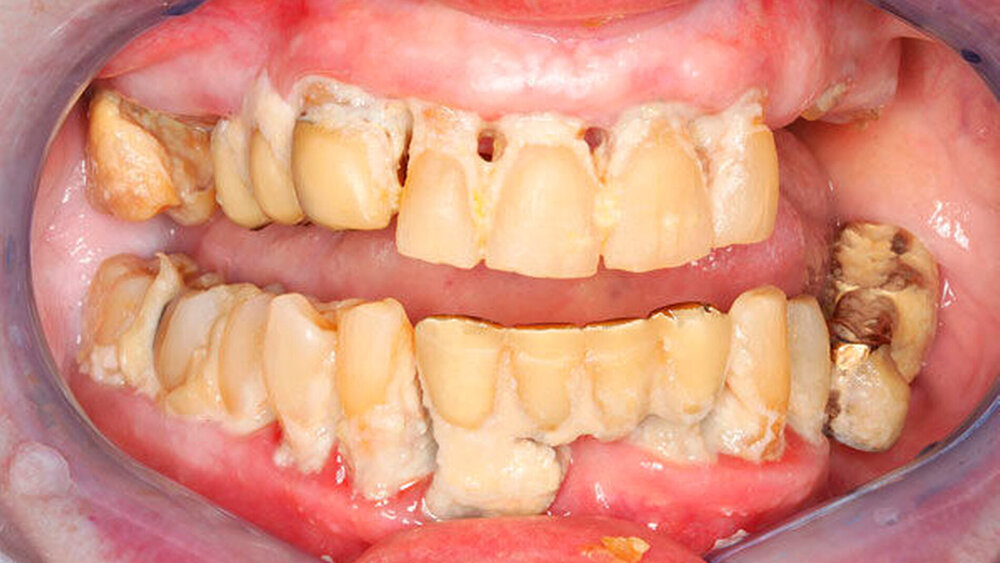

Dabei haben immer mehr dieser immer älteren Menschen immer mehr eigene Zähne, technisch aufwendigen Zahnersatz oder Implantate. Bei pflegebedürftigen Menschen verschlechtert sich der Mundhygienestatus aufgrund eingeschränkt möglicher Hygienemaßnahmen, aufgrund des häufigen Konsums kariogener Speisen und nicht zuletzt auch wegen der vielen Medikamente, die den Speichelfluss reduzieren [Dohlus, 2011; Fitzpatrick, 2000; Nitschke, 2000; Nitschke, 2012].

Die Ergebnisse der fünften Deutschen Mundgesundheitsstudie (DMS V) belegen: 1997 waren 22,6 Prozent der jungen Senioren zahnlos – 2016 nur noch 12,4 Prozent. Pflegebedürftige ältere Senioren haben mehr Karies und Zahnfleischbluten und sie nehmen den Zahnarzt seltener kontrollorientiert in Anspruch [IDZ, 2016].

Beläge und Entzündungen in der Mundhöhle beeinträchtigen die Lebensqualität nicht nur im Sinne von Schmerzen und Mundgeruch, sondern zum Beispiel auch durch ein erhöhtes Risiko für Lungenentzündungen [Müller, 2017]. In Pflegeeinrichtungen sind Lungenentzündungen mit 13 bis 48 Prozent die zweithäufigste Infektionserkrankung, mit 8,8 bis 28 Prozent die häufigste Todesursache und der häufigste Grund für eine Krankenhauseinweisung [El-Solh, 2011; Kreissl, 2008]. Insgesamt weisen Parodontitis-Patienten ein über fünffach erhöhtes Risiko für Lungenentzündungen auf [Awano, 2008]. Die wechselseitige Beeinflussung von Parodontitis und Diabetes sowie mit kardio- und zerebrovaskulären Störungen ist inzwischen ebenfalls gut belegt [Deschner, 2018; Dörfer, 2007; Tonetti, 2007; Taylor, 2008].